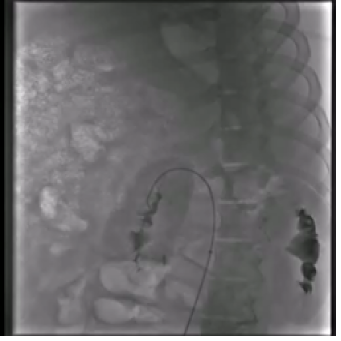

In practice, collecting large-scale data in the medical domain is not a trivial task due to data privacy [10, 11]. To overcome this limitation, federated learning is emerging as a candidate, enabling the training process to occur between hospital silos without collecting patient data. Despite the advantages of federated learning, current challenges include ensuring convergent training across different silos [12] and heterogeneous data [13]. In endovascular intervention, these challenges primarily stem from data gathered from various sources, hence leading to the domain gap between X-ray data. Fig. 1 shows an example of X-ray images from different endovascular datasets. We observe that due to privacy, endovascular datasets with real human X-ray images are usually small, compared to data collected with animal, silicon phantom models, or from simulation environments [14].

(a) Human X-ray

(b) Animal X-ray

(c) Phantom X-ray

(d) Simulation X-ray